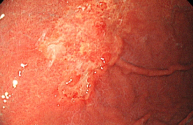

정상 위의 내시경 사진

진행성 위암